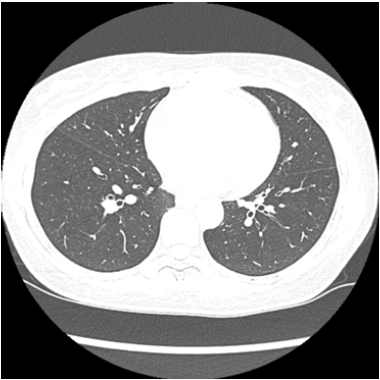

On the 3rd day of disease, with persistent fever, the patient went back to the ER. Peripheral oxygen saturation (SpO2) was 92%, but physical examination remained unremarkable. Coronavirus was confirmed by a positive real-time reverse transcriptase polymerase chain reaction (RT-PCR) assay test from a throat swab specimen after 4 days of the initial symptoms. An unenhanced chest computed tomography (CT) performed on the 3rd day after onset, showed minimal thickening of the bronchial walls, findings that were not suggestive of COVID-19 (Figure 1). On the 4th day ageusia and anosmia started abruptly, even without any previous rhinorrhea or nasal obstruction while both fever and cough resolved. No specific protocol of treatment was instituted. Hidroxicloroquine was considered, but later discarded due to a relative cardiotoxicity contraindication. Olsetamivir was not available and azithromycin was not prescribed. Neither anti-inflammatory drugs nor oral antihistamines were recommended for this acute period. She started to take vitamin B12 BID (5000mcg). She went back to work after a 14 days-hiatus, following a positive IgM and IgG serology. Ageusia and anosmia remained remarkably unimproved until the 20th day from the initial symptoms, when the perception of distinctive flavor, such as spices, started to come back. At that time IgM and IgG serologic tests were positive. Until the end of this report, 30 days from the onset of neuropathy she remained with dysgeusia and hyposmia, even though the serologic profile evolved to that of a chronic phase/resolution with only a positive IgG fraction. As ancillary evaluation, a Sniffin Sticks Test was performed and documented the persistent symptoms (Figure 2).

Figure 1: Unenhanced chest CT of a 54-year-old woman (slice at the level of the base of the lower lobes of the lungs) showed minimal thickening of the bronchial walls.